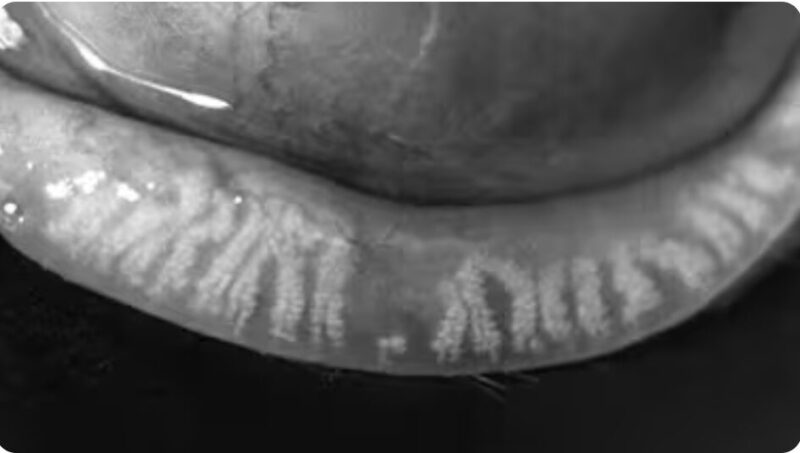

- Geeft een high-definition beeld van de structuur van de meiboomklieren

Beelden LipiScan